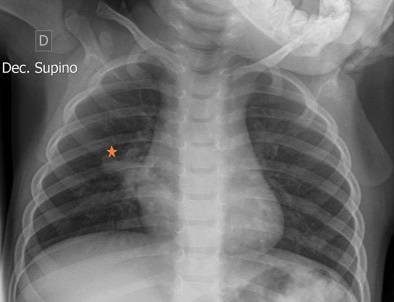

Se solicita por ello radiografía de tórax, con hallazgos que sugieren atresia bronquial derecha con broncocele (Fig. 1). Se realiza ecocardiograma que descarta la presencia de cortocircuitos intracardiacos significativos y muestra con buena función biventricular, así como análisis sanguíneo (hemograma, bioquímica y equilibro ácido-base) sin alteraciones.

Figura 1. Radiografía de tórax en la que se observa atresia bronquial derecha con sospecha de broncocele